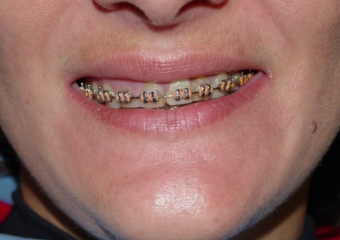

Imagens iniciais observando a ausência do incisivo central superior esquerdo